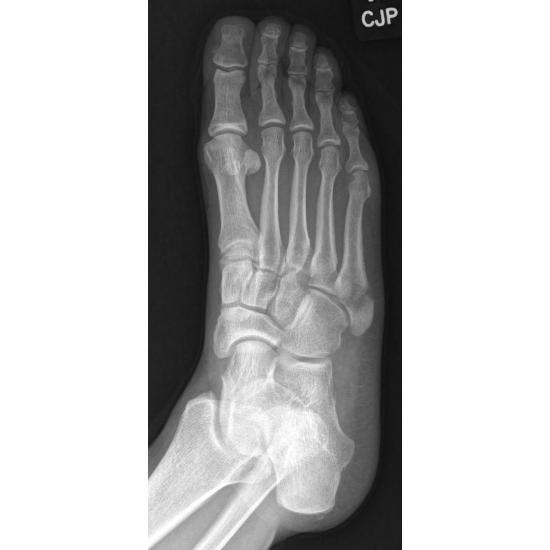

A 48-year-old-female runner complained of right lateral foot pain after running the bases at a softball game. She inverted her ankle on second base and felt a crack, but kept playing afterwards. She initially self-treated with a walking boot, but later went to the sports medicine clinic and was diagnosed with a right fifth metatarsal fracture. Case Photo #1 Case Photo #2